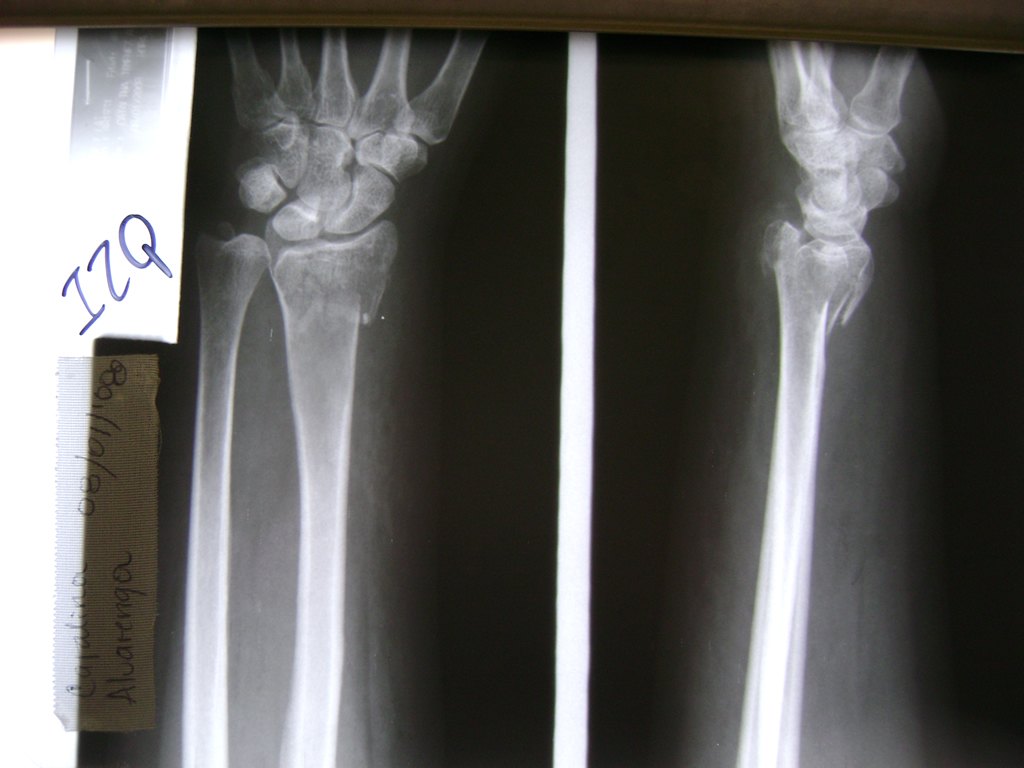

Cirugías de Hombros - Cirugías de Muñecas y Manos

Los procedimientos más comunes en cirugía de la mano son aquellos destinados a reparar traumatismos, incluyendo lesiones de tendones, nervios, vasos sanguíneos, y articulaciones; huesos fracturados; y quemaduras, cortes, y otros daños de la piel.